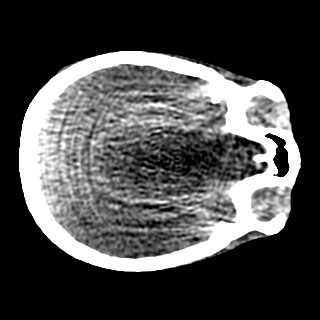

Cone-beam CT (CBCT) employs a flat-panel detector to achieve three-dimensional imaging with high spatial resolution. However, CBCT is susceptible to scatter during data acquisition, which introduces CT value bias and reduced tissue contrast in the reconstructed images, ultimately degrading diagnostic accuracy. To address this issue, we propose a deep learning-based scatter artifact correction method inspired by physical prior knowledge. Leveraging the fact that the observed point scatter probability density distribution exhibits rotational symmetry in the projection domain. The method uses Gaussian Radial Basis Functions (RBF) to model the point scatter function and embeds it into the Kolmogorov-Arnold Networks (KAN) layer, which provides efficient nonlinear mapping capabilities for learning high-dimensional scatter features. By incorporating the physical characteristics of the scattered photon distribution together with the complex function mapping capacity of KAN, the model improves its ability to accurately represent scatter. The effectiveness of the method is validated through both synthetic and real-scan experiments. Experimental results show that the model can effectively correct the scatter artifacts in the reconstructed images and is superior to the current methods in terms of quantitative metrics.